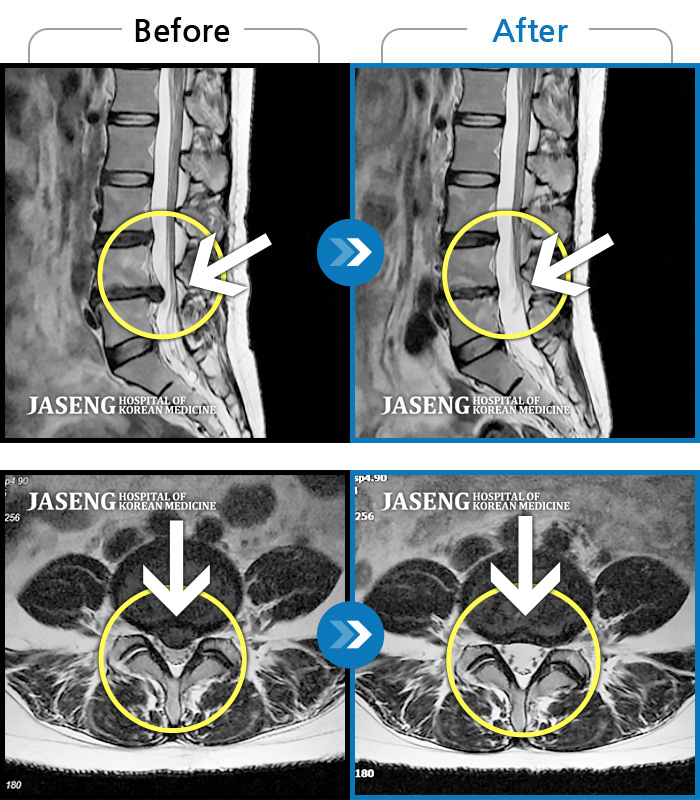

Before

After

환자에게 사전 동의를 받아 동일 조건에서 촬영되었습니다.

개인에 따라 치료 후 부작용이 발생할 수 있으니 의료진과 상담 후 치료를 진행하시기 바랍니다.

요통과 우측 하지부 당김 증상

디스크 파열 후 허리 골반 통증, 허리 숙일 때 다리 당김 증상